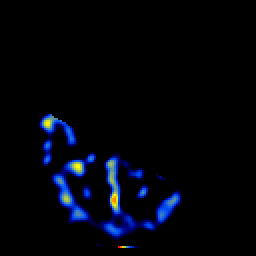

SPECT TL Study #5 -- Slice #15

[Home][Help][Clinical][Tour 1][Tour 2][Tour 3] Slice 15